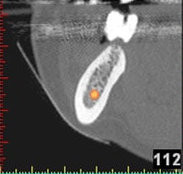

3D-Implantatplanung - Detailaufnahme 1

3D-Implantatplanung - Detailaufnahme 2

3D-Implantatplanung - Detailaufnahme 3

3D-Implantatplanung - Detailaufnahme 4

3D-Implantatplanung - Detailaufnahme 5

3D-Implantatplanung - Detailaufnahme 6

3D-Implantatplanung - Detailaufnahme 7

3D-Implantatplanung - Detailaufnahme 8

3D-Implantatplanung - Detailaufnahme 9